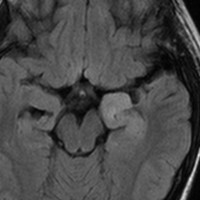

小児の良性の神経節膠腫 ganglioglioma グレード1(真の腫瘍)

7才の時に音読でつかえるようになり,眼で何かを追っているような欠伸発作(左側頭葉てんかん)を繰り返すようになり,強直間代発作を生じて腫瘍が発見されました。下側頭回底面の皮質に発生した境界明瞭な腫瘍であり,周囲に脳浮腫を伴っています。T2強調画像で線維成分の多い硬い部分は低信号に,軟らかい部分はやや高信号となり,ガドリニウムでheterogenousに増強されます。グレード1の神経節膠腫としては非典型的な画像所見で術前診断は難しいもので,PXA pleomorphic xanthoastrocytoma も疑いました。もちろん治療としては開頭手術での全摘出です。術後に発作は消失しています。